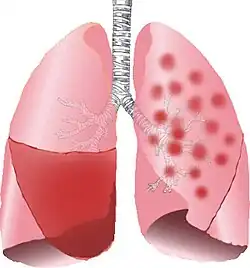

| Typical distribution of lobar pneumonia (left in image) and bronchopneumonia (right in image) | |

Bronchopneumonia is a subtype of pneumonia. It is the acute inflammation of the bronchi, accompanied by inflamed patches in the nearby lobules of the lungs.[1]

It is often contrasted with lobar pneumonia; but, in clinical practice, the types are difficult to apply, as the patterns usually overlap.[2] Bronchopneumonia (lobular) often leads to lobar pneumonia as the infection progresses. The same organism may cause one type of pneumonia in one patient, and another in a different patient.

On gross pathology there are typically multiple foci of consolidation present in the basal lobes of the human lung, often bilateral. These lesions are 2–4 cm in diameter, grey-yellow, dry, often centered on a bronchiole, poorly delimited, and with the tendency to confluence, especially in children.